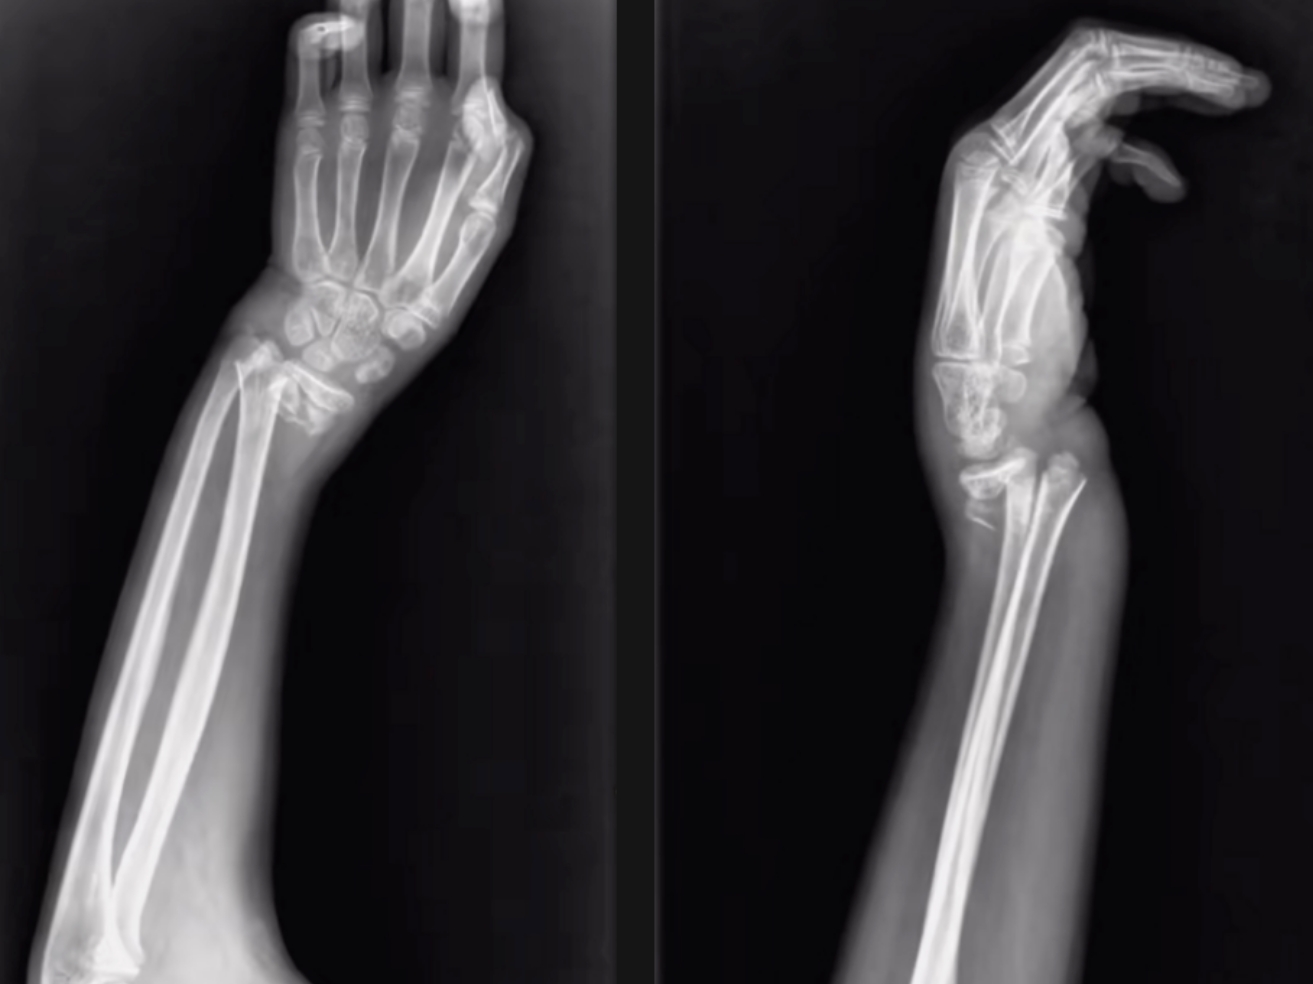

橈骨遠(yuǎn)端骨折復(fù)位前 橈骨遠(yuǎn)端骨折復(fù)位后